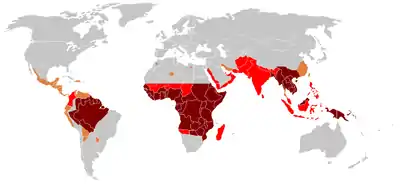

Épidémiologie

- Prévalence élevée de la chloriquino-résistance ou multi-résistance

- Chloriquino-résistance présente

- Pas de Plasmodium falciparum ou de chloriquino-résistance

- Pas de paludisme

Dans les années 1990, le paludisme était annuellement la cause de 400 à 900 millions de cas de fièvres, et entre 700 000 et 2,7 millions de morts[92], soit en moyenne un mort toutes les 30 secondes[93]. En 2012, entre 473 000 et 789 000 personnes sont mortes du paludisme[94]. La grande majorité des victimes sont des enfants de moins de 5 ans[95],[94], les femmes enceintes étant aussi particulièrement vulnérables car le placenta constitue une cible où les parasites (Plasmodium falciparum) peuvent s'accumuler. Malgré les efforts entrepris pour réduire la transmission de la maladie et améliorer son traitement, il y a eu peu d'évolution depuis le début des années 1990[96]. La mortalité semble décroître depuis la fin des années 2000 et est estimée à 1,2 million de personnes en 2010[97].

Le paludisme est endémique dans les zones intertropicales dans les Amériques, dans de nombreux endroits d'Asie, et dans la plupart de l'Afrique. C'est toutefois dans l'Afrique sub-saharienne que l'on trouve 85 à 90 % des morts du paludisme[100]. La distribution géographique de la maladie au sein de grandes régions est complexe, et l'on trouve ainsi des zones paludiques et non paludiques proches l'une de l'autre[101]. Dans les régions sèches, les périodes de paludisme peuvent être prédites sans trop d'erreurs en utilisant les cartes de précipitation[102]. À l'opposé de la dengue, le paludisme est davantage présent dans les campagnes que dans les villes[103]. Par exemple, les villes du Viêt Nam, du Laos et du Cambodge sont pratiquement exemptes de paludisme, mais celui-ci reste présent dans les campagnes[104]. En 2016, d'après l'Organisation mondiale de la santé, aucun cas de paludisme n'a été recensé au Sri Lanka durant trois années consécutives ; c'est donc le deuxième pays du Sud-Est asiatique, après les Maldives, à avoir éradiqué le paludisme[105]. La Chine est devenue le le quarantième territoire ayant éradiqué cette maladie[106]. En Afrique en revanche, le paludisme est présent aussi bien dans les zones rurales qu'urbaines, même si le risque est diminué dans les grandes villes[107]. Les niveaux endémiques mondiaux de la maladie n'ont pas été cartographiés depuis les années 1960. Cependant, le Wellcome Trust britannique finance le Malaria Atlas Project[108] afin de rectifier ceci et d'évaluer le poids de cette maladie à l'avenir.